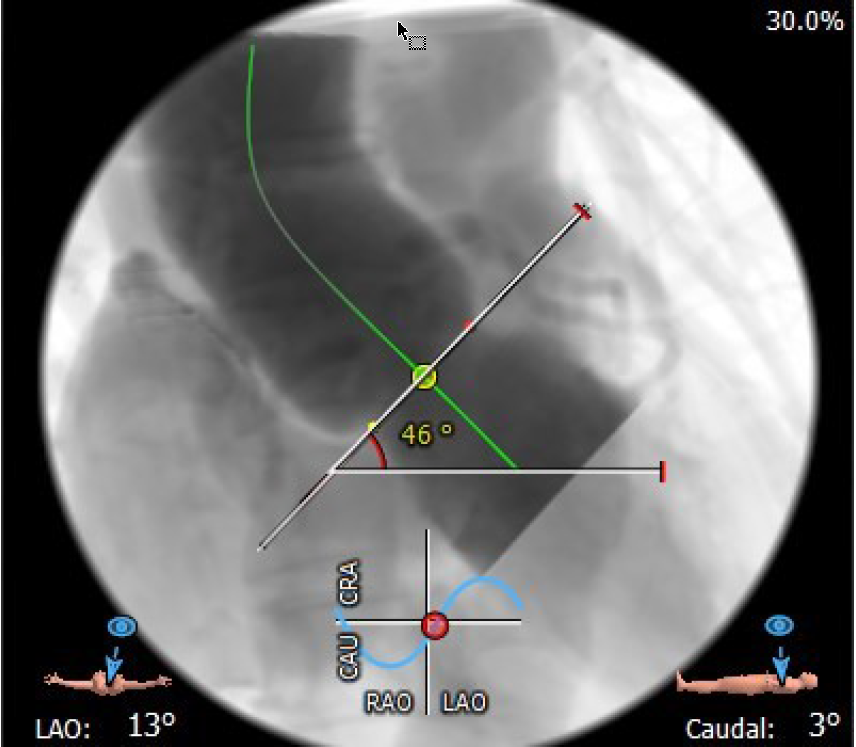

4.患者术中造影角度LAO:13°,CAU:3°;

投照角度:LAO13°CAU3°